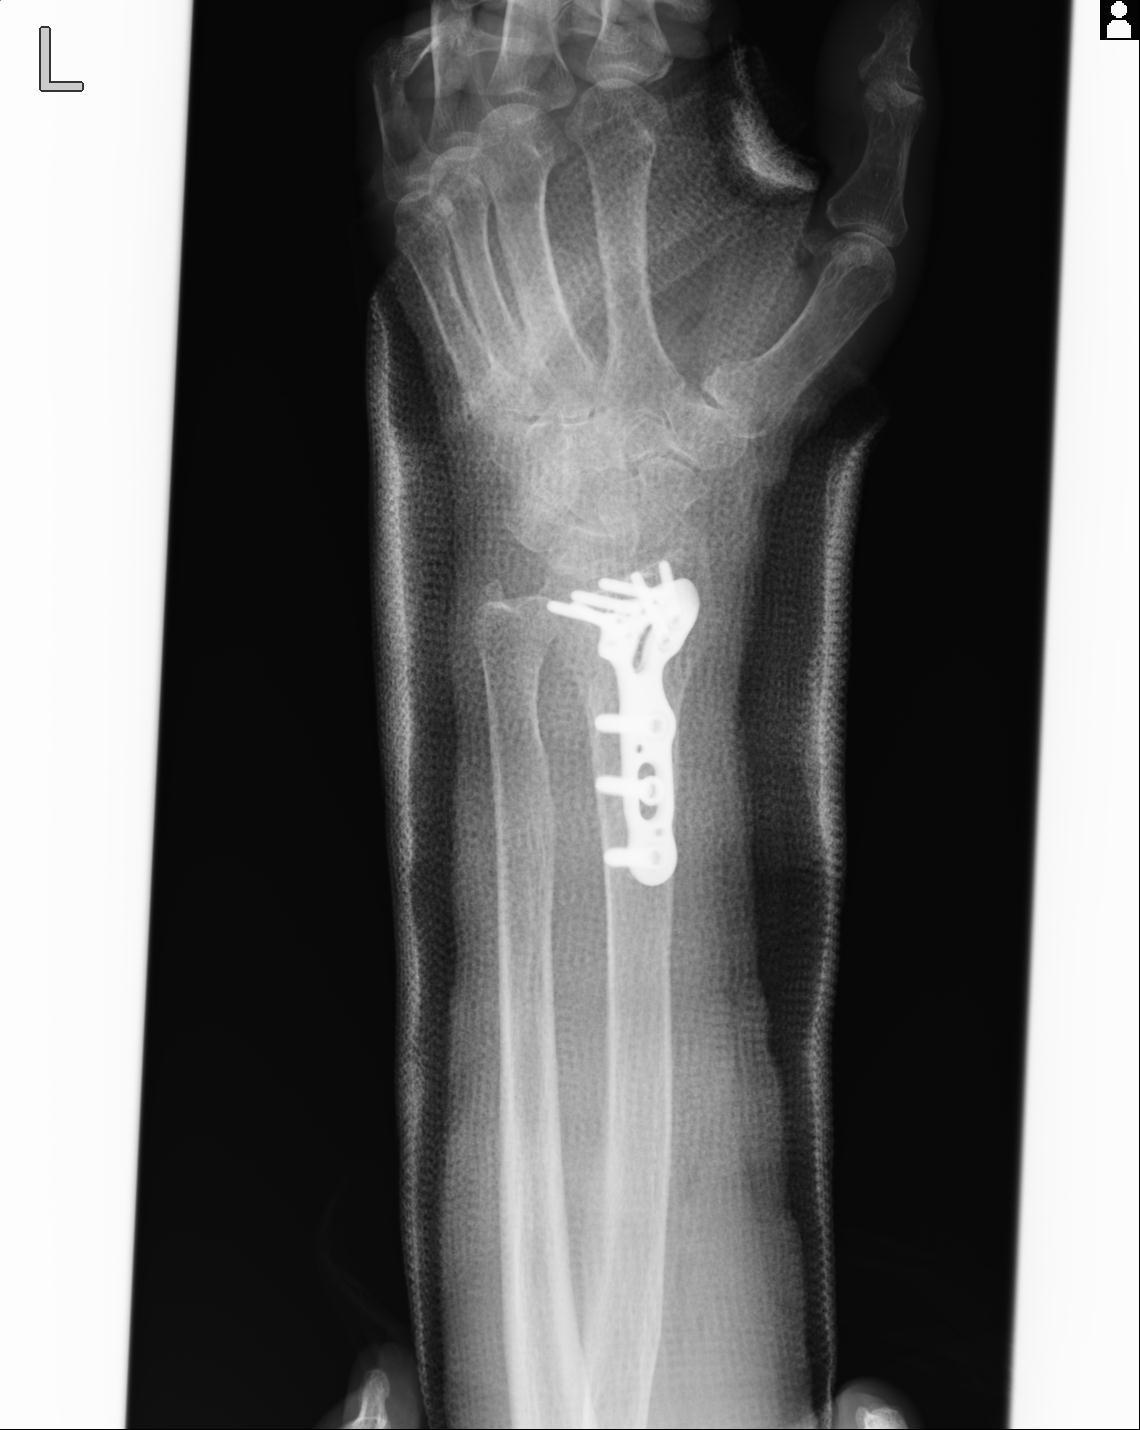

102766 1/5 1/12 左手関節 4R 28歳男性 左橈骨遠位端